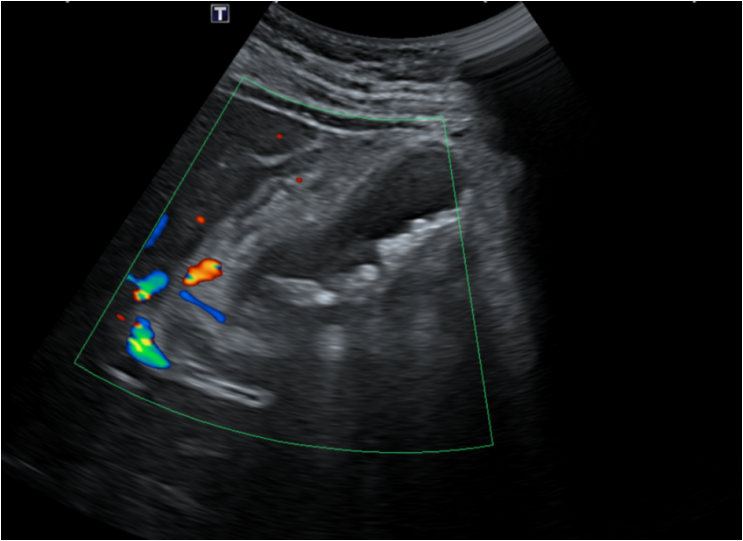

진료 후 기본 피검사, 복부초음파로 확인을 하였고, 복부 초음파상에서 담낭 주위로 지저분한 에코와 여러 개의 담낭 돌을 확인할 수 있었습니다. 이는 급성 담낭염의 전형적인 소견으로 피검사상에서도 염증수치가 많이 올라가 있었습니다. 결석성담낭염 진단, 급성 담낭염은 수술적인 치료까지 필요한 상황이라 상급병원으로 전원을 하였습니다.

• 복부초음파: 담낭 주위 지저분한 에코와 담낭 돌 복부초음파: 담낭 주위 지저분한 에코와 담낭 돌

• 복부초음파: 결석성담낭염 소견 (컬러도플러) 복부초음파: 결석성담낭염 소견 (컬러도플러)